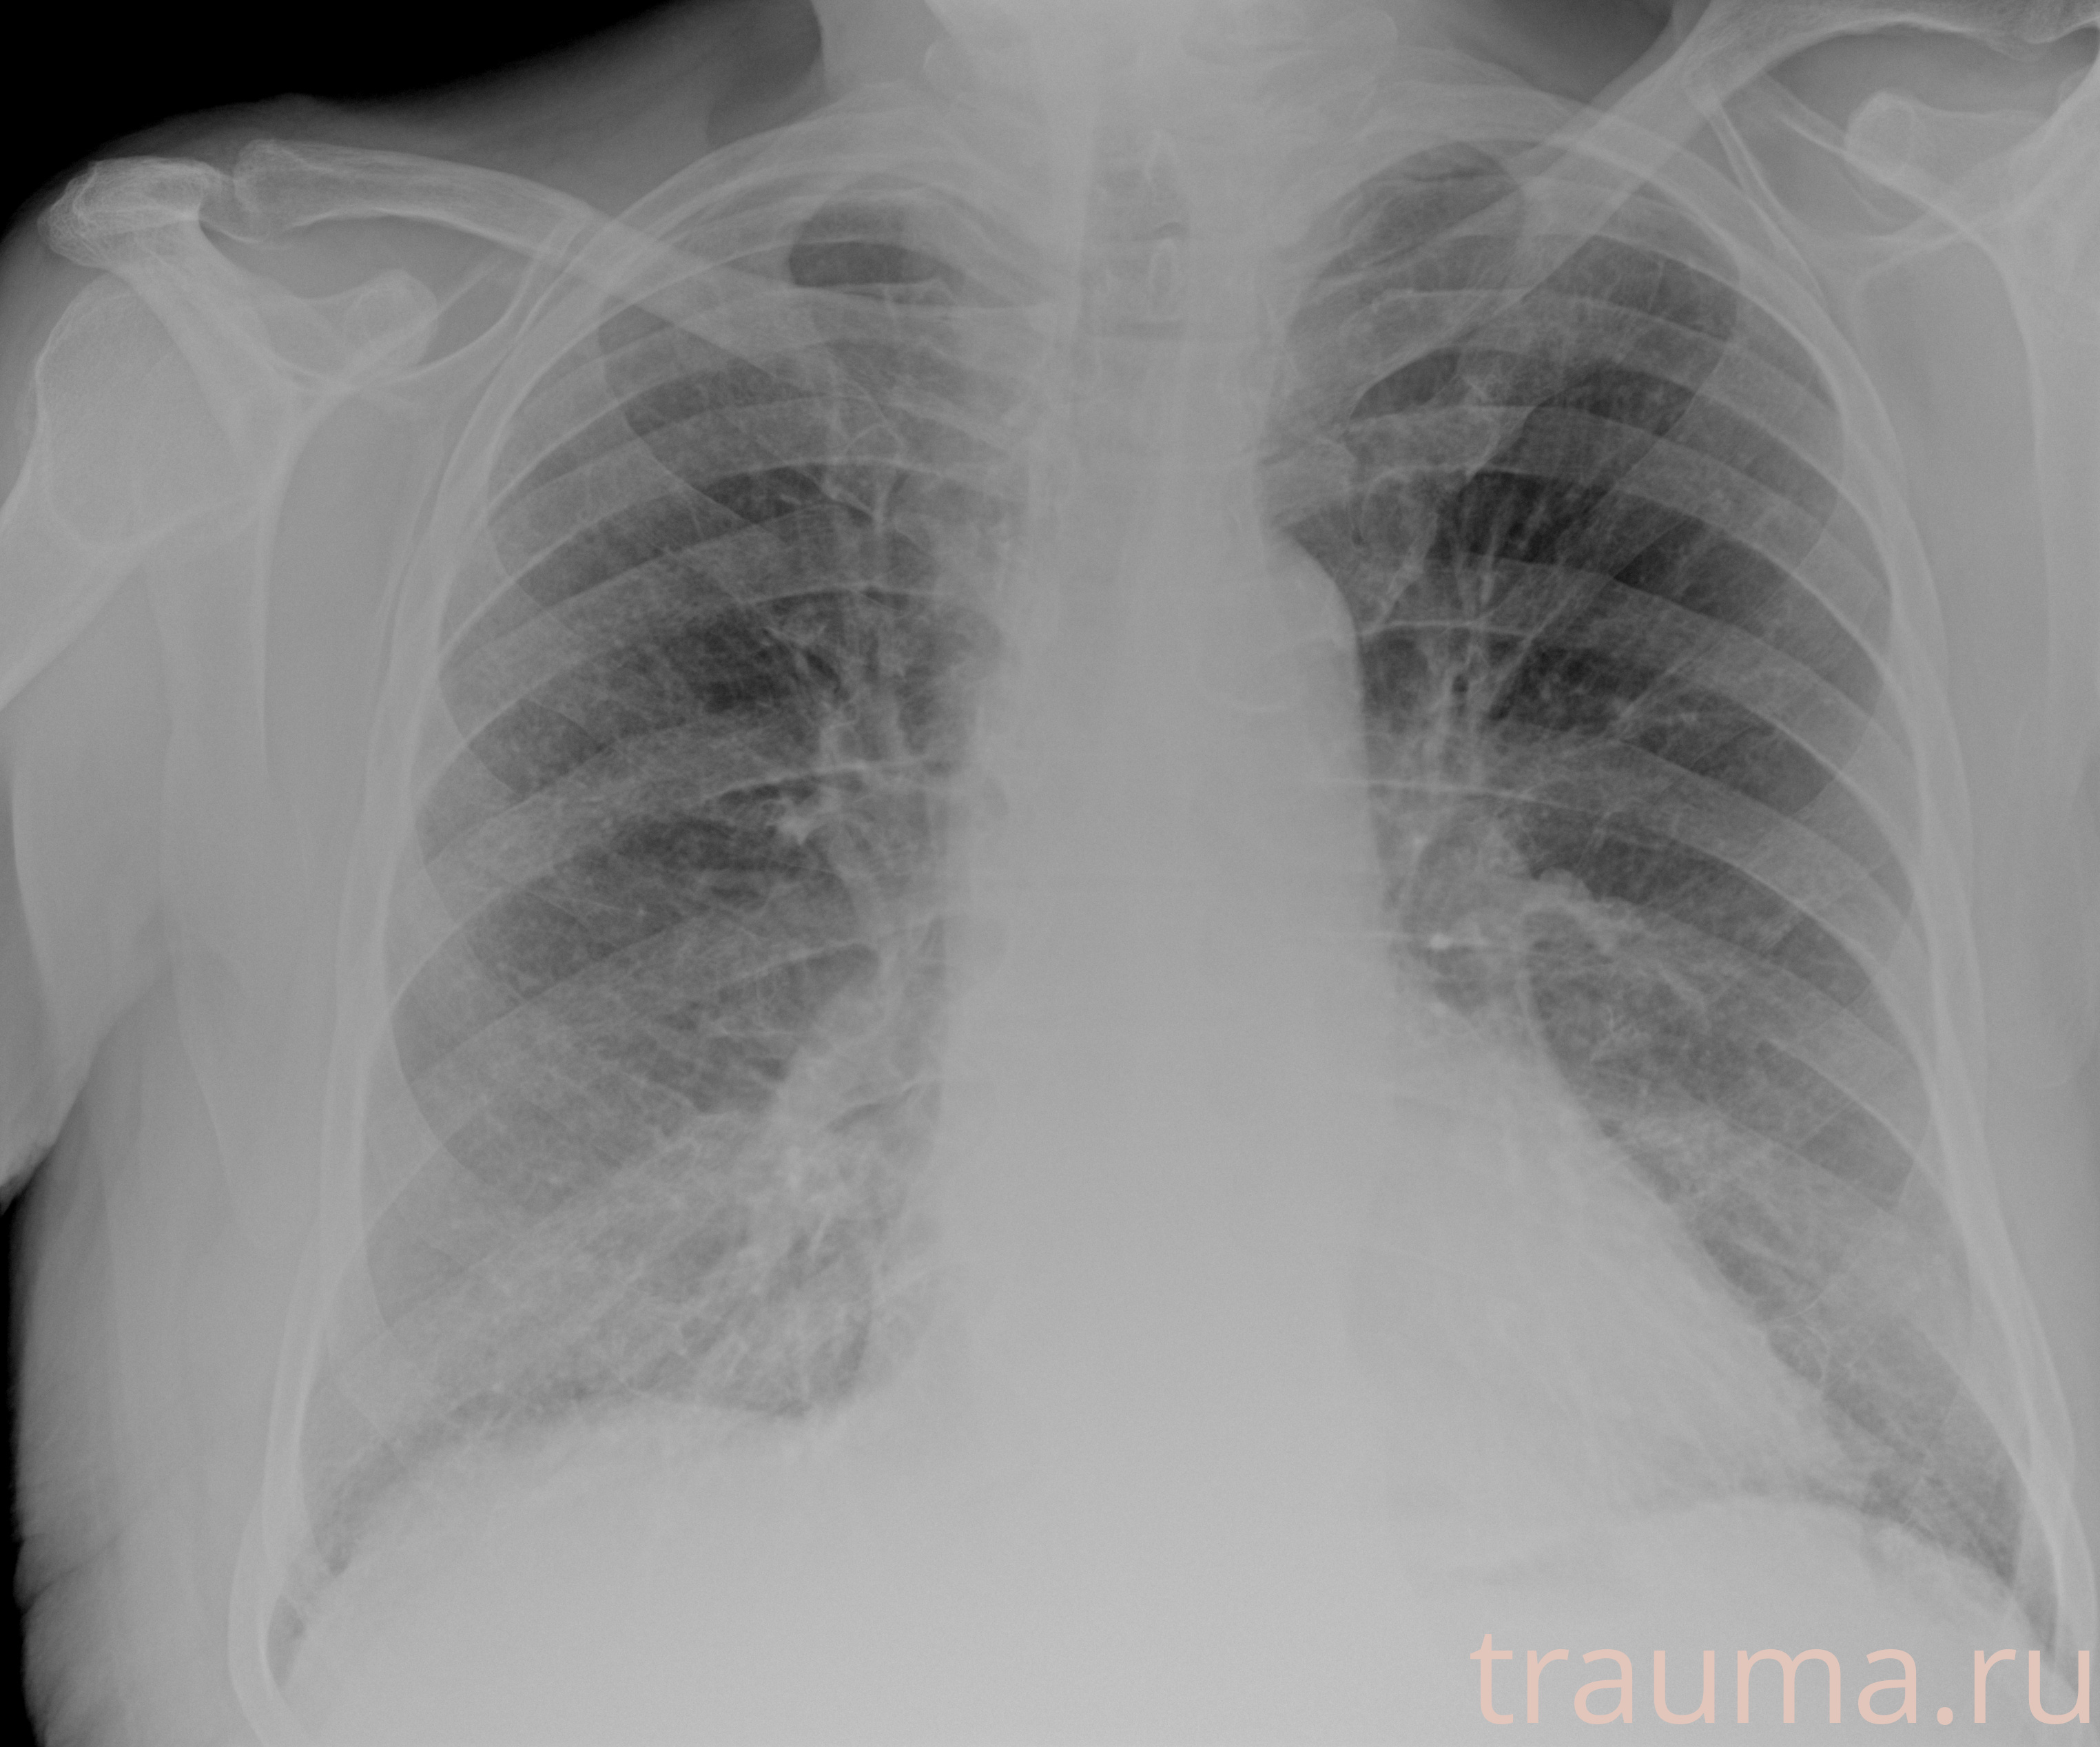

Рентгенограммы

Рентген на дому: по вашему адресу приезжает врач-рентгенолог, травматолог-ортопед с мобильным рентгеновским аппаратом, проводит диагностику травмы или заболевания, делает необходимые рентгенограммы, дает рекомендации по дальнейшему лечению. Получить качественные снимки в домашних условиях возможно благодаря уникальной методике, разработанной МосРентген Центром для института  Склифосовского

Яркость: 1   Контраст: 1   Инвертировать: 0 Увеличение: 1

Перетаскивайте мышь вверх/вниз для контраста, влево/право для яркости. Прокрутка колесом изменяет масштаб. Нажмите Сбросить для возврата к исходному изображению. При увеличении держите мышь в той области, которую хотите рассмотреть.